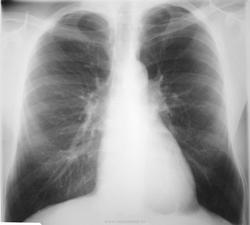

Форма и размеры срединной тени в пределах нормы, правда талия сглажена. В малом круге кровоток несколько уменьшен - корневые ветви артерий истончены. Венозного застоя нет. Правые отделы сердца не страдают. Левые камеры - незначительная гипертрофия левого жеудочка, вероятна гипертоническая болезнь. Узур в ребрах нет - коарктация аорты маловероятна. Казуистика - типа миксом левого предсердия по обзорным снимкам - недоказуема, но хорошо видна именно на УЗИ.

Соглашаясь, в целом, с Анатолием Владимировичем в описательной части, тем не менее, добавлю вот какой ньюанс- "заострение" кардиовазального угла в левой боковой проекции и "выбухание", как бы локально, восходящей аорты в начальном ее отделе.

Без клинических данных действительно сложно. По рентгенкартине: легочный рисунок близок к норме, корни не настораживают. Слабо выражена дуга оарты для возраста пациента, признаки гипертрофии левого желудочка, хотя и не кричащие. В восходящей аорте (по переднему контуру) локальное выпячиванние (указано Виктором Григорьевичем). Рискну предположить наличие у больного аортального стеноза.

Увы, классическая рентгенология здесь буксует, не случайно так разошлись мнения классиков. Но лично я считаю что здесь «слишком хорошо» видны лёгочные вены. Правда, только справа. Небольшой поворот пациента влево способствовал этому. А вот увеличения левого средостения, которое должно быть при данном пороке выражено и о котором пишут узисты, не вижу.

- Согласно данным ЭХО, неполноценной является только одна створка митрального клапана, и возможной причиной этого является разрыв доп. хорды, удерживавшей створку ранее. Регургитация есть, значительная, но всё же не такая, как если бы недостаточными были обе створки клапана, со вторичным расширением митрального отверстия...

Почему не произошло ремоделирования (увеличения) миокарда?

- Во-первых, вследствие сдерживающего давления эмфизематозно изменённых лёгких. Во-вторых, в связи с недостаточным износом самого миокарда. Да, срыв компенсаторных механизмов может произойти в любое время, но ещё не случился. В том числе вследствие своевременной диагностики патологии и соблюдении рекомендаций охранительного режима...

Забыл написать: предстоящая операция – протезирование митрального клапана.